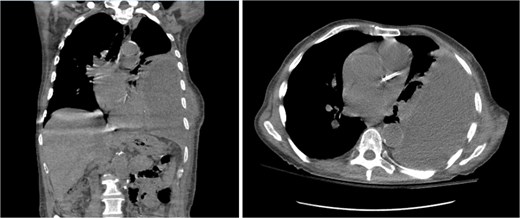

On presentation, chest radiography (Fig. 1) showed a large loculated left pleural effusion, and computed tomography (CT) scan (Fig. 2) confirmed the presence of the effusion with extension into the chest wall. The patient appeared ill with increased work of breathing. Physical exam revealed a large, fluctuant area with a solid component superior to the previous chest tube site, with no overlying skin changes. Blood work was significant for hyponatremia to 127 and a white blood cell count of 10.3 with no neutrophilic predominance. The patient was admitted, started on IV antibiotics, and dual antiplatelet therapy was held in preparation of surgical treatment of his EN. During this time, the fluctuant mass developed an opening, creating a pleurocutaneous fistula, and began to drain significant purulent fluid, which was sent for bacterial cultures.

Initial chest radiograph showing a large loculated left sided pleural effusion.